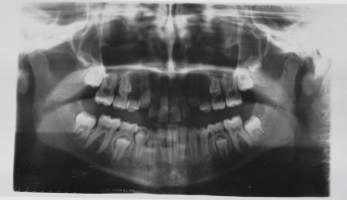

Ortopantomografia röntgenkuvia / laite-esittelykuvia 5 kpl erä

Nykyaikainen hampaiden panoraamakuvaus (eli ortopantomografia, OPTG) perustuu suomalaisen professorin Yrjö Paateron ja diplomi-insinööri Timo Niemisen kehitysyöhön. Ensimmäiset laitteet valmisti Palomex.